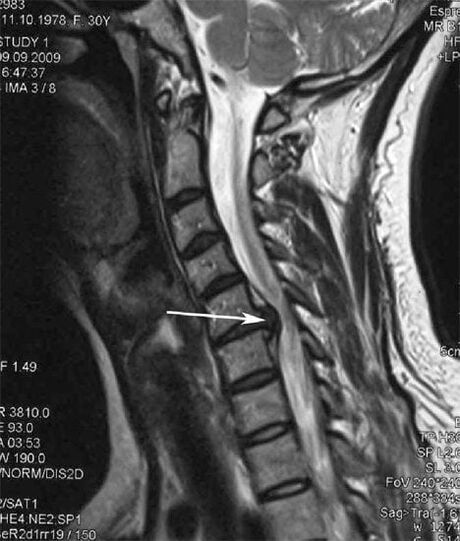

Nelle fasi iniziali, l'osteocondrosi viene rilevata mediante risonanza magnetica. Successivamente, la patologia può essere diagnosticata mediante radiografia. Nelle radiografie della colonna cervicale, diventano evidenti una diminuzione della distanza tra le vertebre, cambiamenti patologici nelle articolazioni delle faccette e osteofitosi.

Molte persone si lamentano di non riuscire a girare il collo a causa del forte dolore che appare dopo aver sollevato improvvisamente qualcosa di pesante. Questo fenomeno indica la formazione di un'ernia del disco. La causa del dolore alla schiena, al collo e agli arti superiori è il pizzicamento di una delle radici nervose che emergono dal midollo spinale.

| Osteocondrosi cervicale | La comparsa di cambiamenti patologici in uno o più segmenti di movimento spinale. Mobilità spinale compromessa, sviluppo di sindromi dolorose miofasciali e pizzicamento delle radici spinali | Dolore, parestesie e disturbi motori nella regione cervicale, che si estendono alla parte posteriore della testa e agli arti superiori. Rilevazione di cambiamenti caratteristici nella colonna vertebrale alla risonanza magnetica e alle radiografie (osteofiti, diminuzione della distanza tra le vertebre, segni di danno alle articolazioni intervertebrali) |